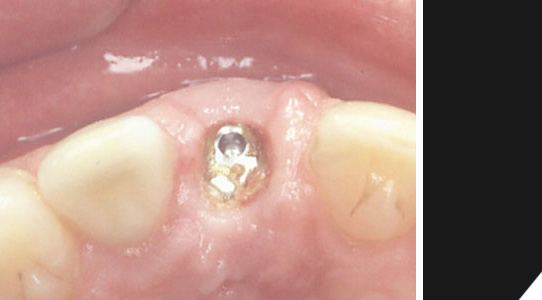

Nach der Einheilphase wird ein Pfosten für die Befestigung der Krone in das Implantat eingeschraubt.

Eine Übergangslösung wird für eine kurze Zeit eingesetzt.